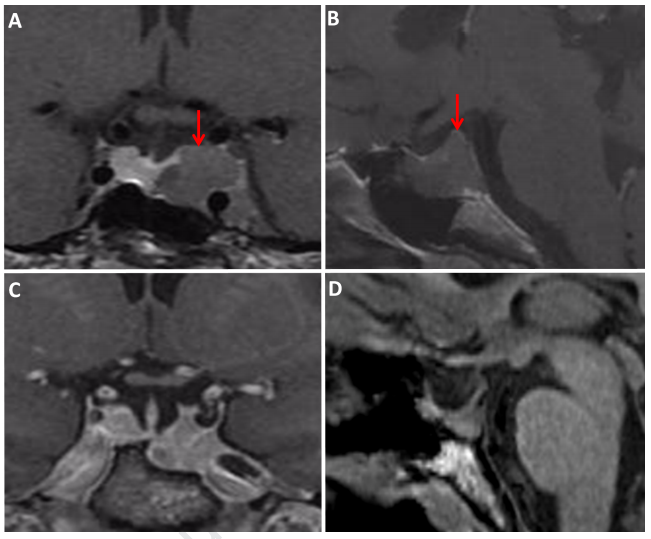

患者为29岁女性,有肢端肥大综合征病史。大腺瘤在另一家医院的一开始手术中被部分切除。患者因激素改变就诊。神经系统检查未显示视力受损或其他缺陷。MRI显示鞍区占位性、增强性肿块,大小为15×17×12 mm,伴海绵窦浸润(Knosp III和Hardy II)[图1]。经蝶窦入路进行内窥镜手术,几个月后,对侵犯海绵窦的残留肿瘤进行放射治疗。

图1